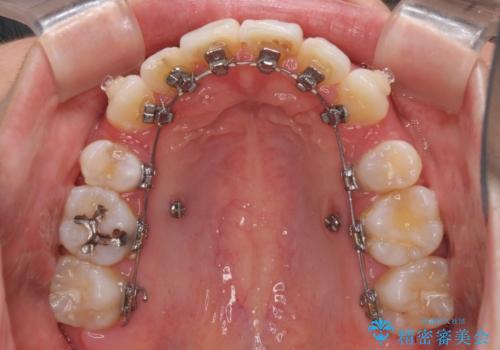

目立たないハーフリンガル矯正 抜歯矯正で口元を改善

- ハーフリンガル

- 前歯のデコボコと上顎の前突感による口の閉じにくさを気にして来院された患者様です。

目立たない装置を希望されたので、上顎が裏側装置のハーフリンガルを選択し、上下左右の小臼歯(計4歯)を抜歯して矯正治療を行うこととしました。

治療期間の目安は3年~3年半でしたが、咬み合わせにより上顎のスペースがなかかな閉じきらず、治療期間が長期化してしまいました。